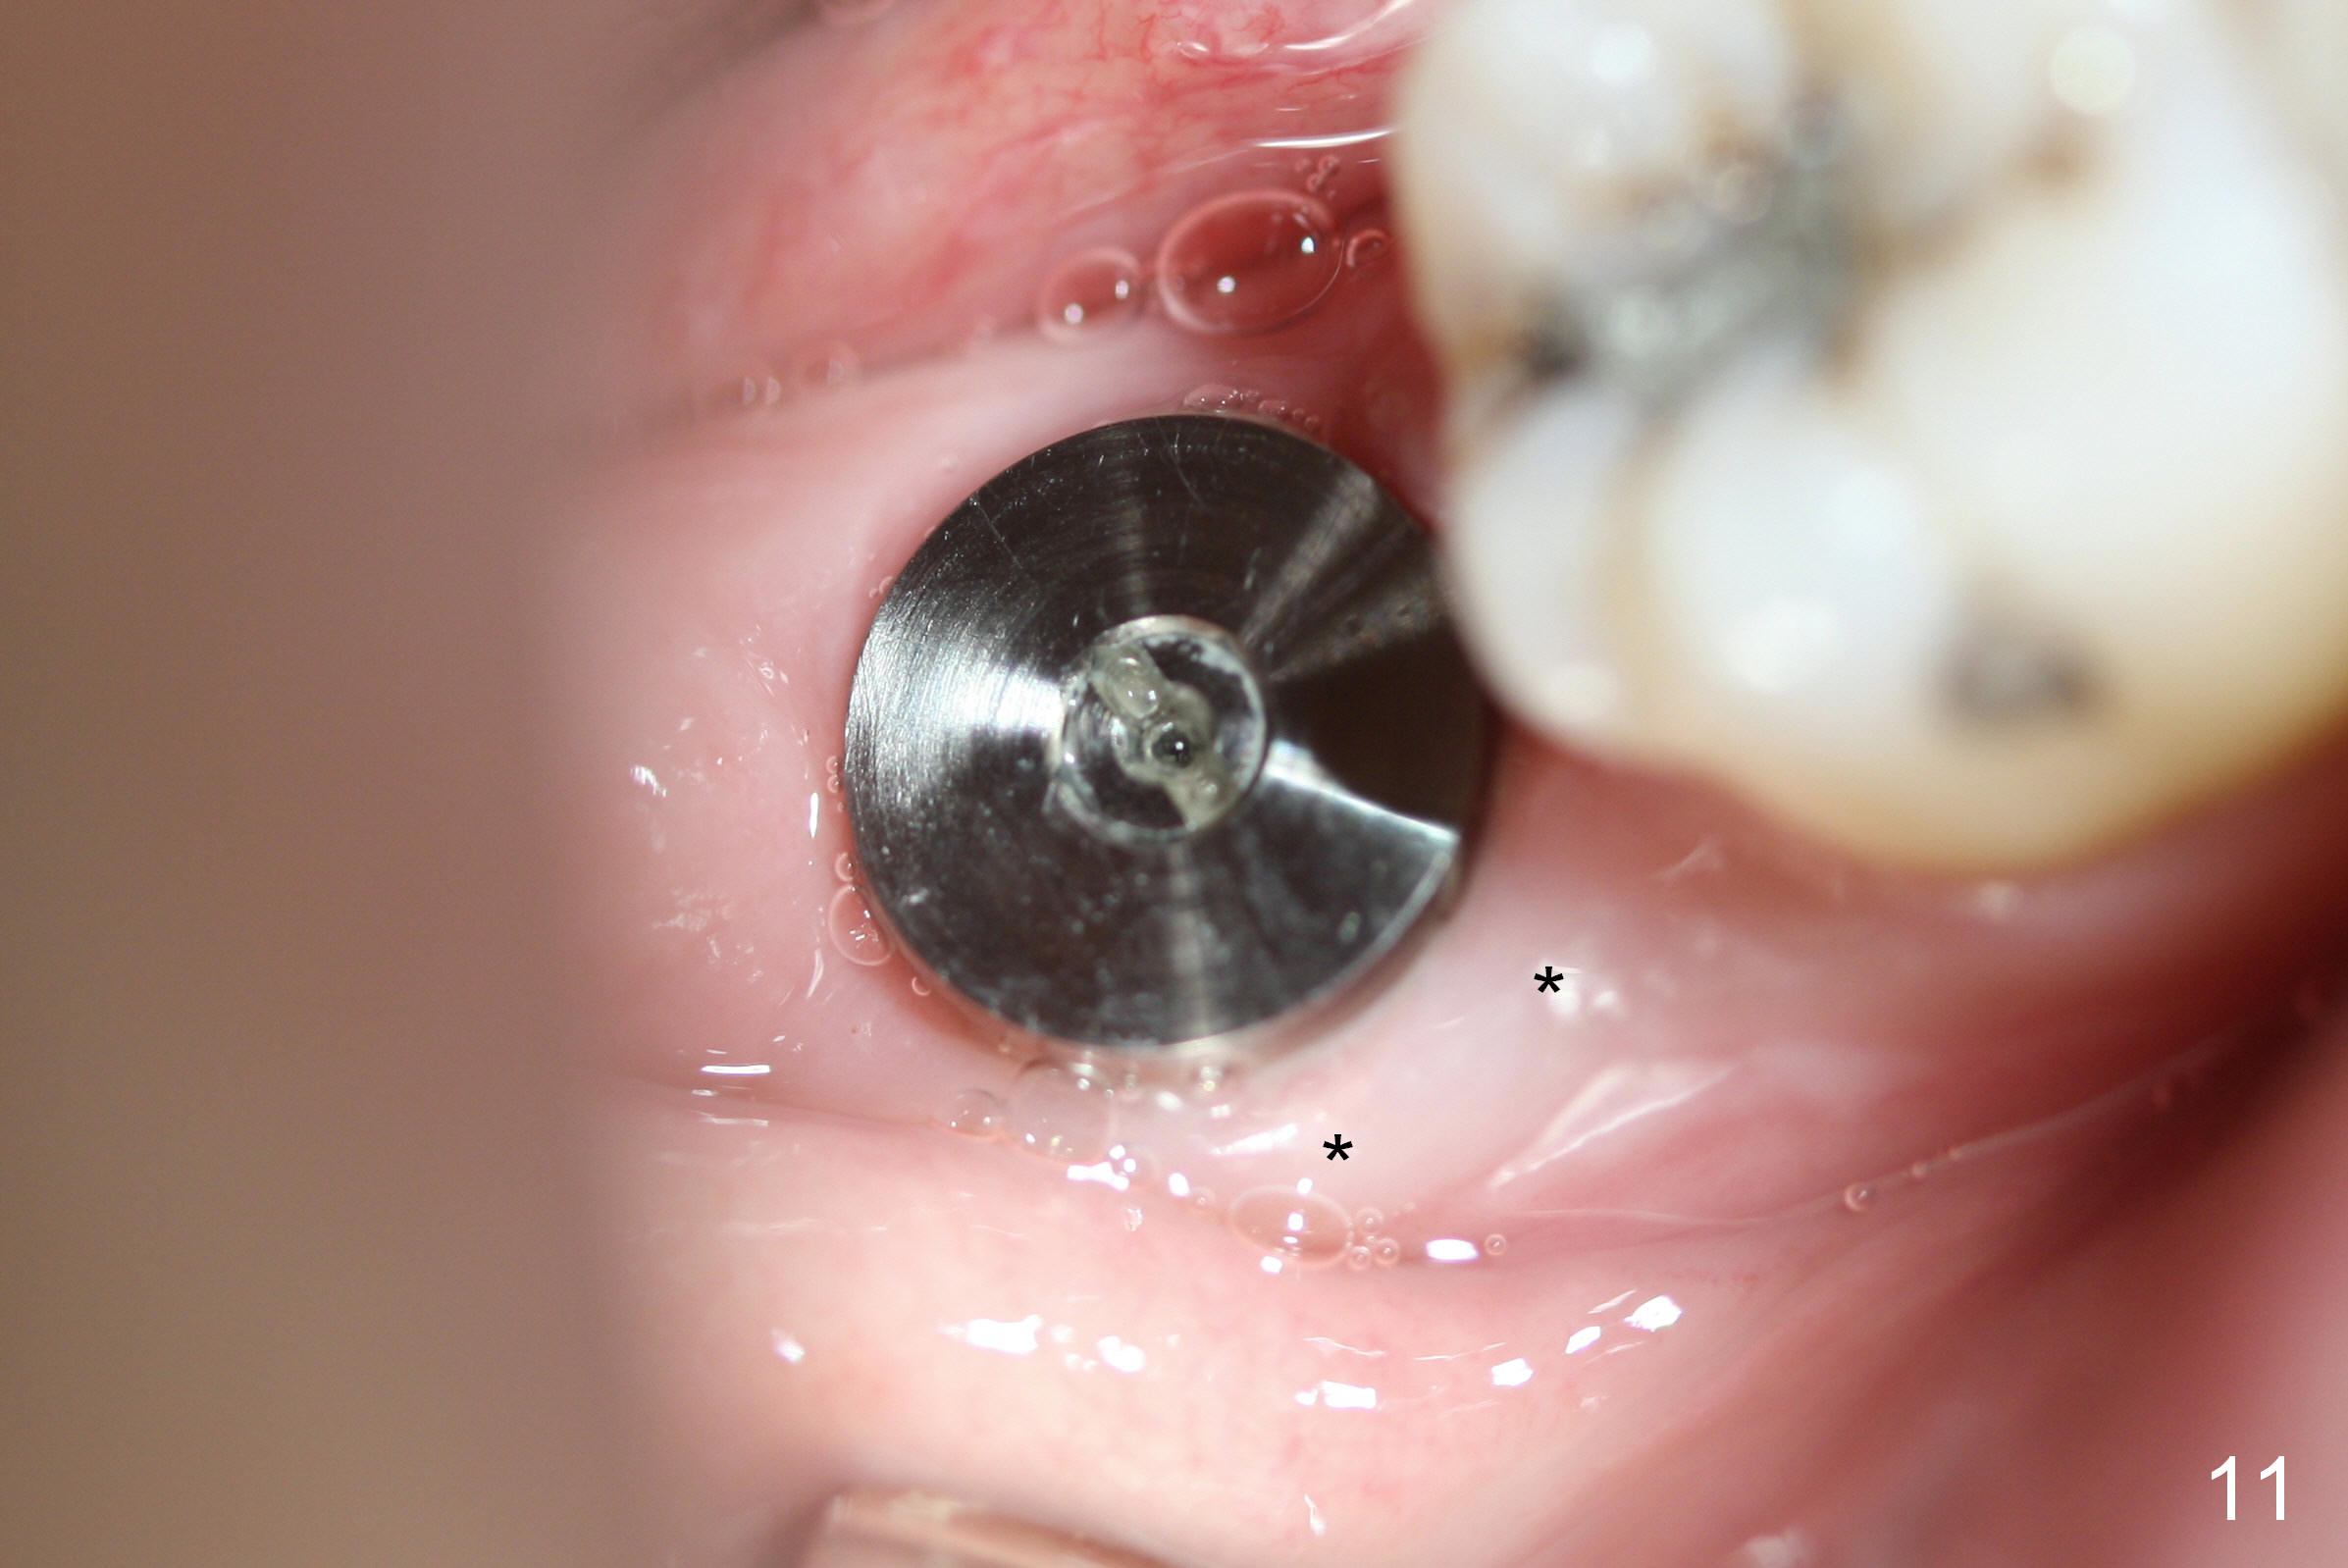

The patient returns 22 days postop (Fig.8-10). The gingiva heals around the implant. There is excess lingual gingiva (Fig.9,10 *), which should recede gradually. Fig.7 is an illustration (from Fig.4) to show how the socket is closed.. A suture is placed (black line) to approximate buccal (black arrow) and lingual (white arrow) gingiva distal to the implant (blue circle).

The gingiva forms a band (cuff) around the implant (Fig.11 *) and bone has apparently filled the peri-implant gap (Fig.13 *) 3.5 months postop. The gingival cuff is present immediately pre-crown cementation (Fig.12 *). The bone density around the implant continues to increase 2 and 7 months post cementation (Fig.14,15), in spite of retention of residual cement distally (<).